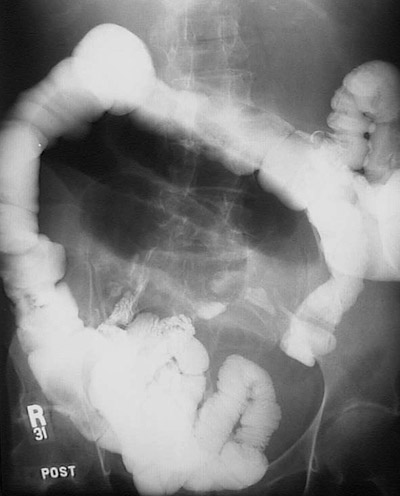

This upper GI series demonstrates obstruction of the small intestine from an adhesion between loops of bowel that formed following abdominal surgery years before.